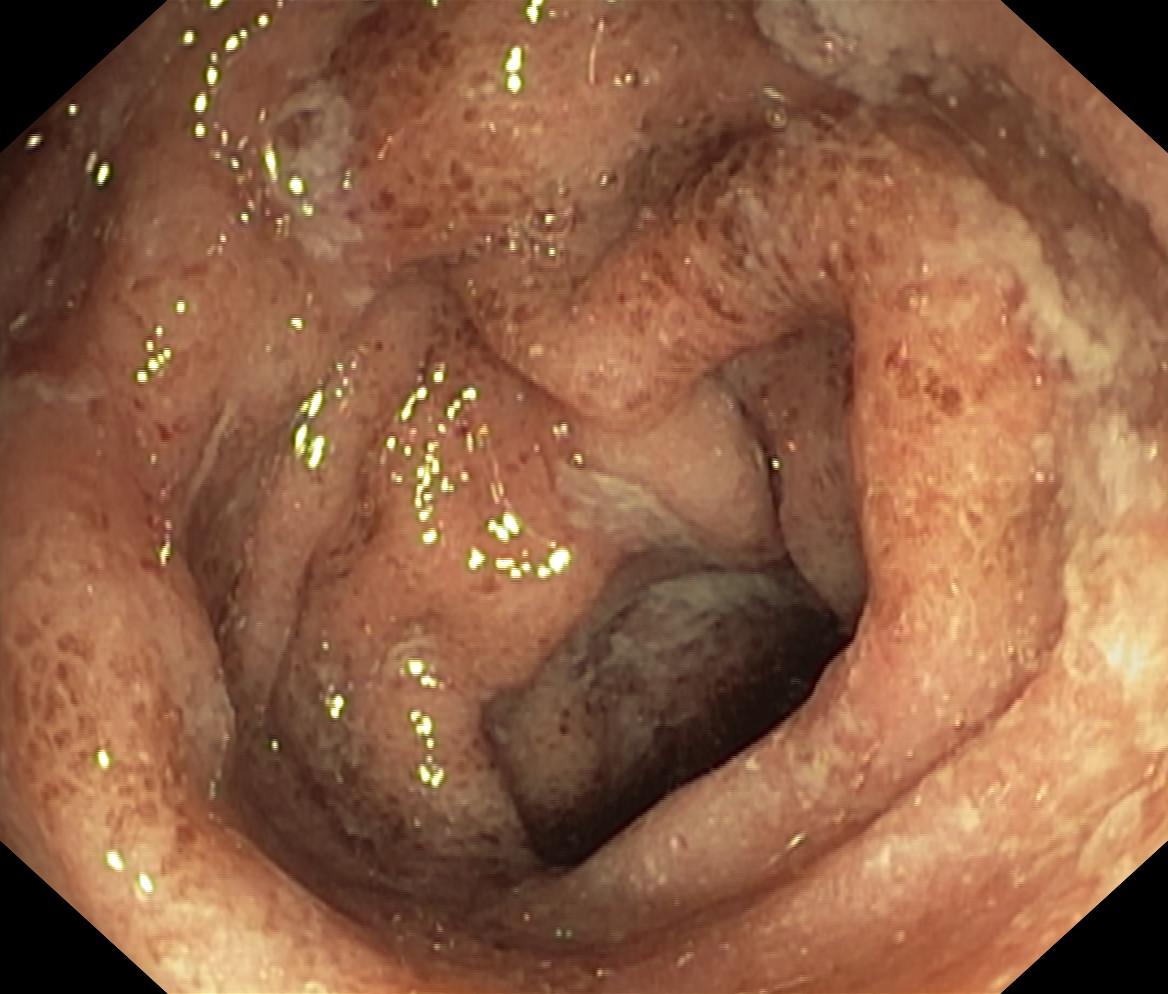

Obrazy endoskopowe

Nowotwory przewodu pokarmowego